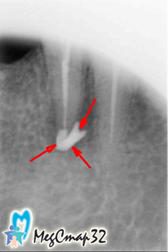

После проведенных операций во второе и третье посещения были сделаны

контрольные снимки (сн.№2 сн.№3) на которых стало заметно

уменьшение воспалительных явлений.

Через три недели со времени первого посещения в канал и за его верхушку,

был введен препарат для восстановления костной ткани около корня зуба (сн.№4).